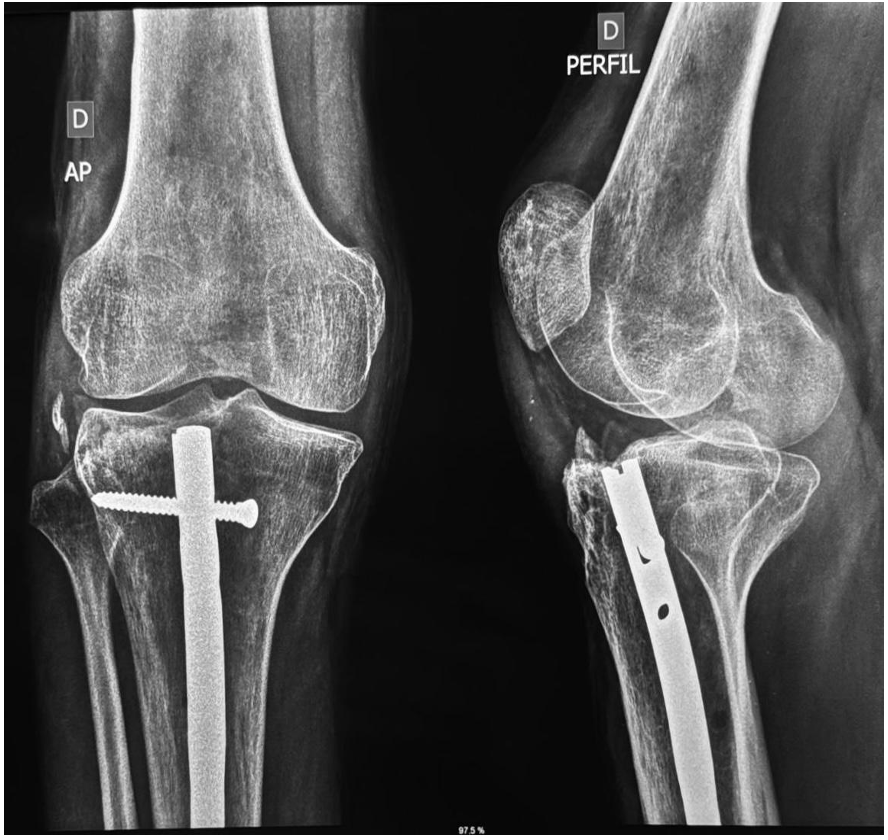

Figura 5 – Radiografia demonstrando osteossíntese de joelho direito

Descrição: Radiografia AP e perfil realizada pós 180 dias de evolução de osteossíntese com haste centralizada e bem-posicionada. Sinais indiretos de calcificação do complexo ligamentar colateral lateral.

Fonte: Banco de dados do Hospital de Base Dr. Ary Pinheiro – HBAP.

O manejo inicial seguiu protocolos do ATLS, com redução das luxações, fixação externa e tração, seguido de exames complementares que confirmaram fraturas intrarticulares e lesão ligamentar. A intervenção definitiva incluiu osteossíntese da tíbia (Figura 5), manejo conservador das fraturas pélvicas e acompanhamento ambulatorial com fisioterapia para reabilitação articular e recuperação neurológica parcial.